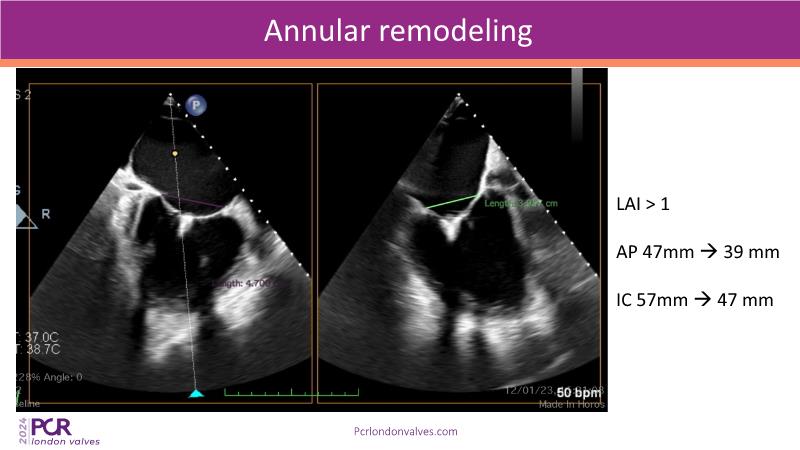

This session on mitral regurgitation offers an in-depth look at the EMPOWER trial outcomes, indirect annuloplasty in aFMR, and remodeling with the CARILLON device. Explore the benefits of early treatment for secondary mitral regurgitation, understand the role of left ventricular reverse remodeling, and review the latest clinical evidence supporting indirect annuloplasty. Discover how this technique keeps future treatment options open while expanding therapeutic possibilities for aFMR.

- To understand the importance of early treatment of secondary mitral regurgitation and the clinical benefits associated with left ventricular reverse remodeling